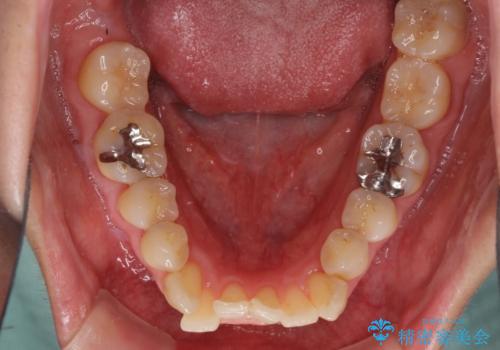

- 前歯のデコボコを気にして来院された患者様です。

上下前歯の先端同士が接触する切端咬合であったため、上顎は歯列を拡大し、下顎はIPR(歯と歯の間を削る)により叢生を解消しながら歯列を小さくすることとしました。

矯正装置にはインビザラインを用いることとしました。

治療途中に前歯に歯髄充血を思わせる痛みが認められたため、無理のない歯の移動と頻繁な経過観察を行いました。

切端咬合はスムーズに解消され、前歯の負担を軽減させることができました。